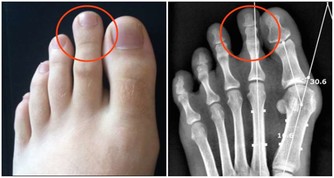

輕微缺乏維生素B2人體不會有任何感覺,但到一定程度時就會出現明顯的症狀,首先,在人體最薄弱的地方,通常是消化道的首尾兩端,即口腔或肛門的局部,出現充血、腫脹,隨後皮膚或粘膜出現潰瘍,然後開始出血,這即是口腔潰瘍和痔瘡。如果長期缺乏維生素B2,那麼人體其它部位也會出現同樣的症狀。

主要原因在於血管,構成血管壁的細胞離不開維生素B2,當缺乏維生素B2時,血管壁(主要是毛細血管,管壁本身就很薄)開始變薄,在血壓的作用下,血管開始向外凸起,當局部的血管都開始鼓起時,就形成了腫塊,最後血管開始裂開出血,如果發生在腦部,你猜到了嗎?對,這就是腦溢血。